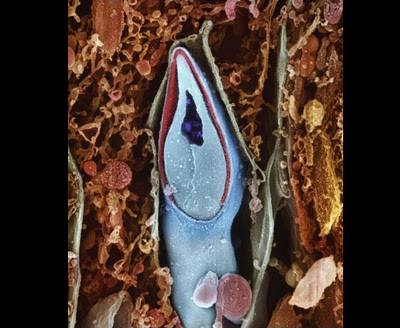

Սպերմատոզոիդն արգանդափողում

Ֆալոպյան փողը, որի միջով բեղմնավորված ձվաբջիջն անցնում է դեպի արգանդ: